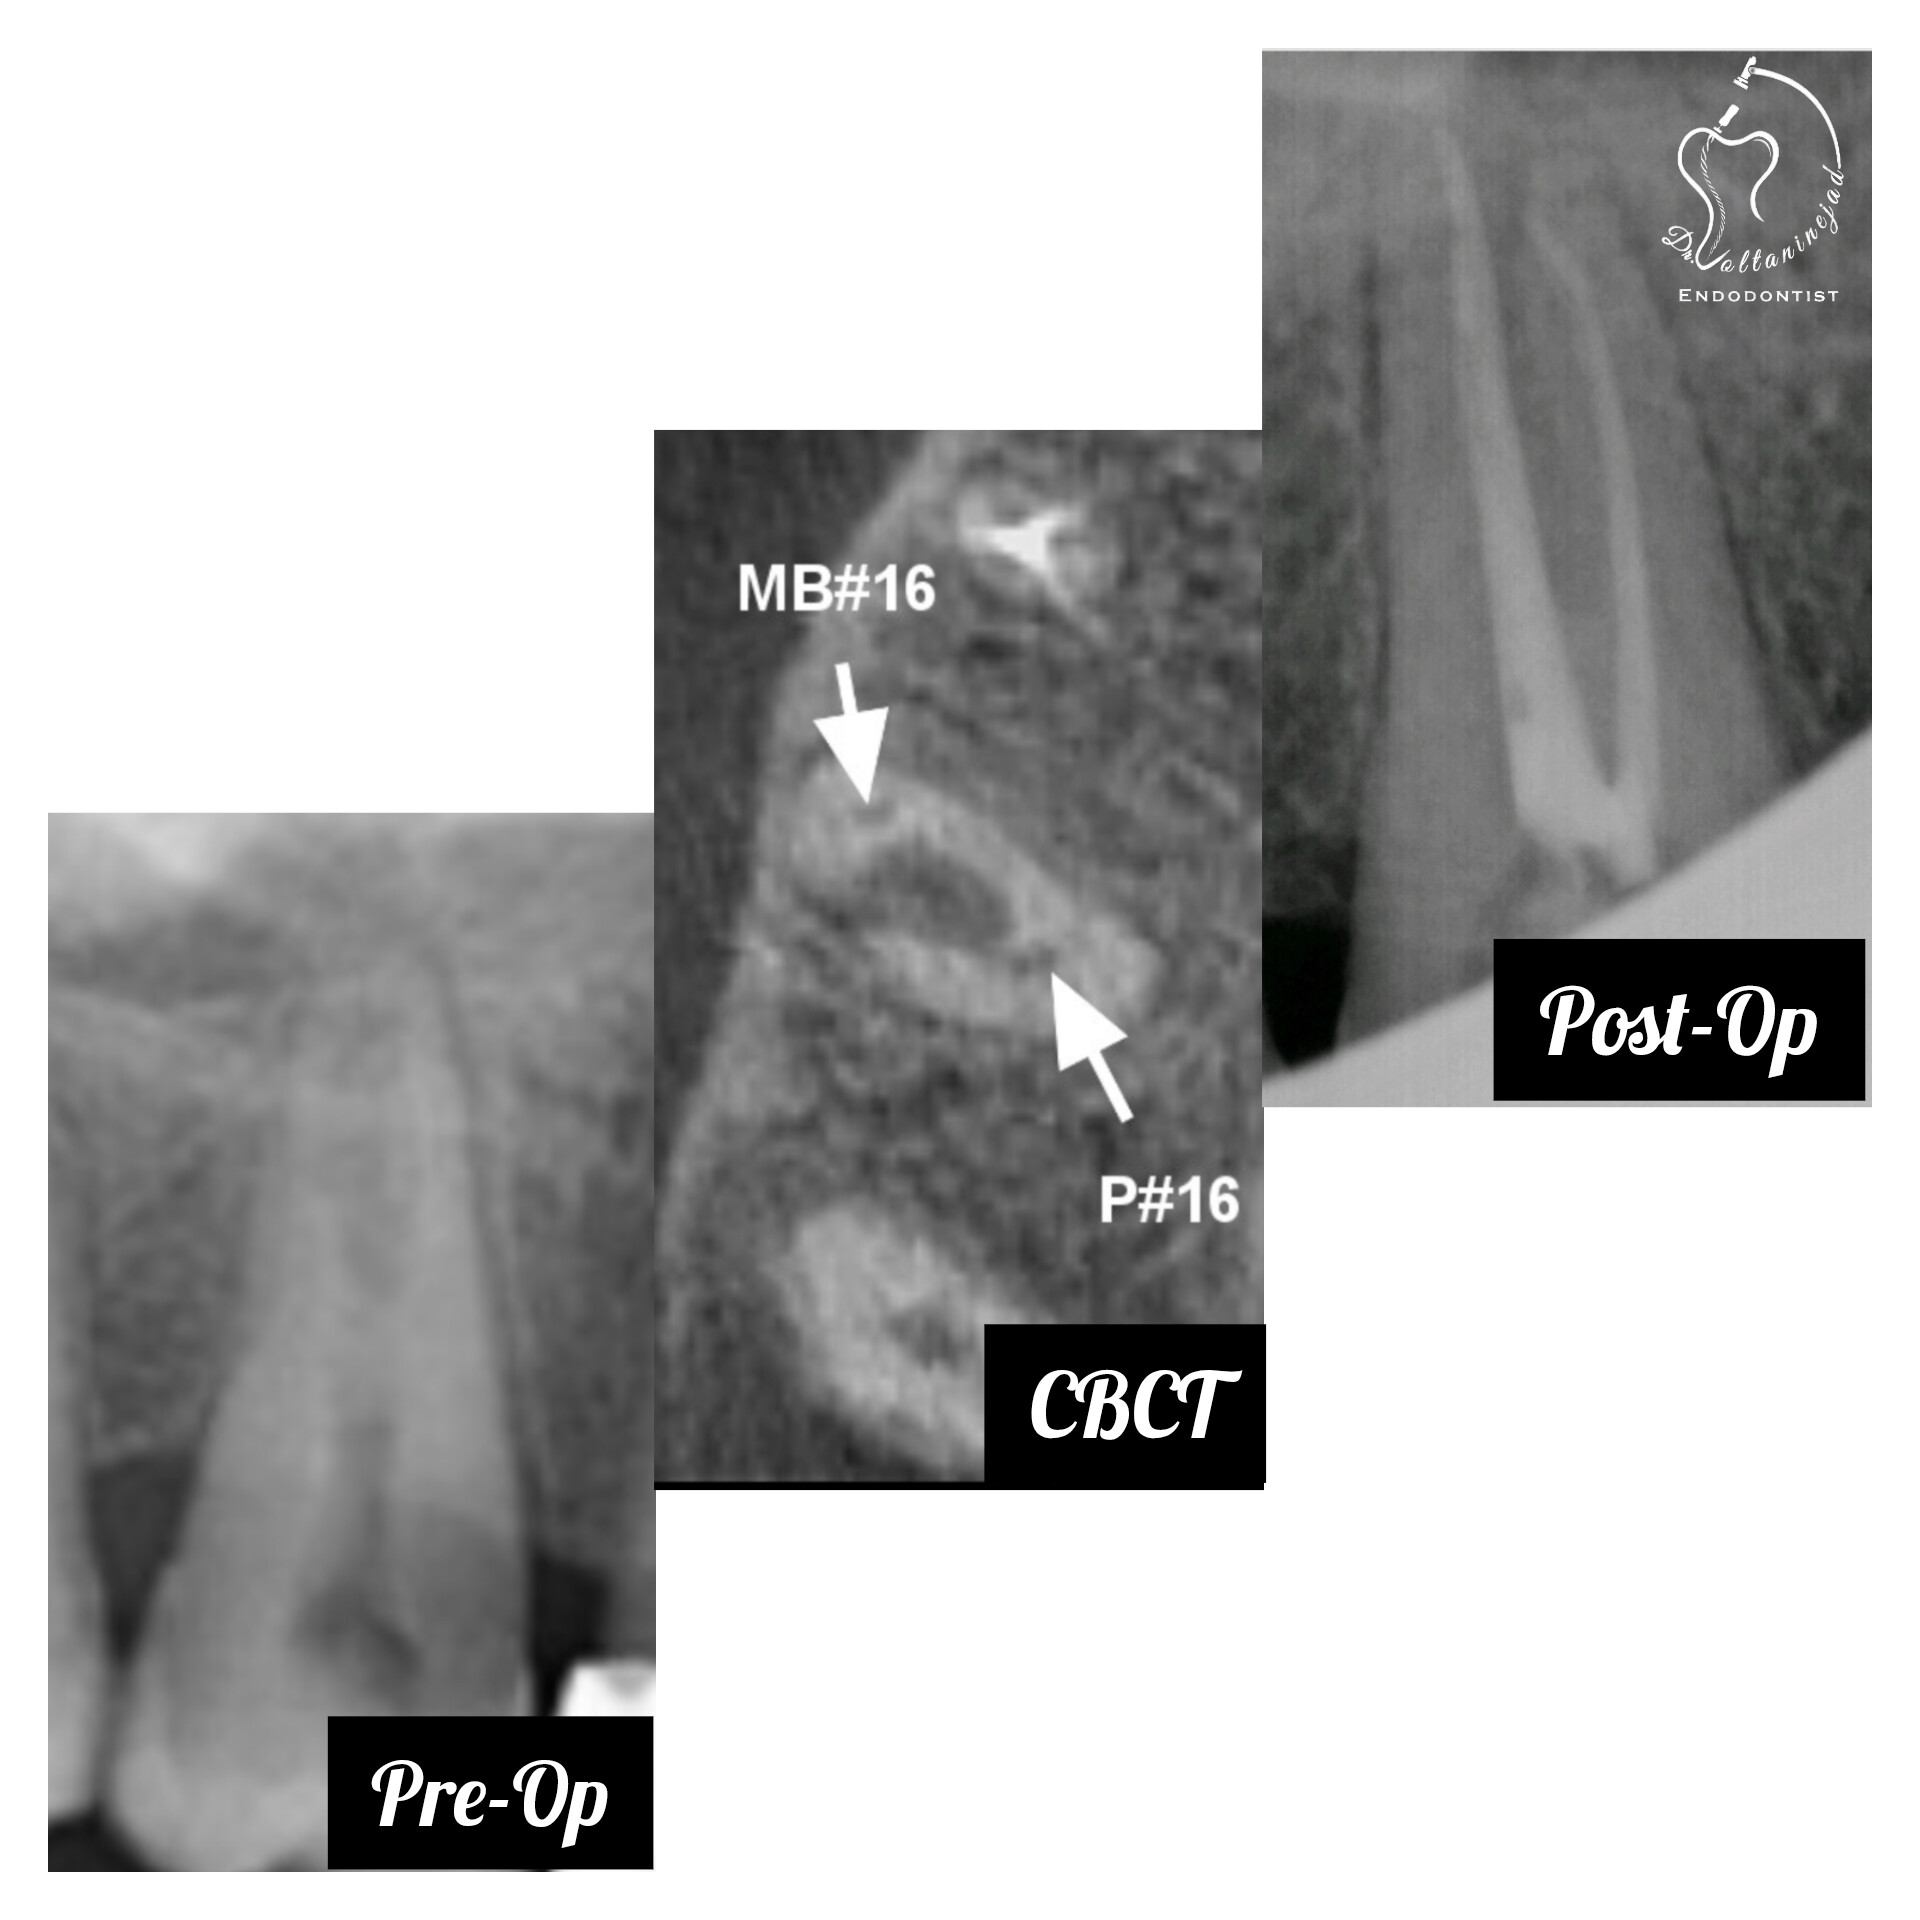

🔹 درمان ریشه دندان دائمی نابالغ با انتهای ریشه باز و آبسه مزمن در کودک ۸ ساله

• شرح کوتاه: کودک ۸ ساله با دندان دائمی نابالغ عفونی و آبسه مزمن مراجعه کرد که درمان ریشه تخصصی میکروسکوپی با موفقیت انجام شد.

• نتیجه: حذف ضایعه مقاوم و حفظ دندان به مدت طولانی.

درمان ریشه دندان نابالغ